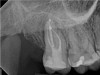

In the first case study, a young female patient was told she had a tooth (tooth No. 2, Figure 3) that should be extracted due to extensive bone loss. Using CBCT, the clinician was able to identify a large lateral canal within the palatal root. Despite the bone loss, the patient was eager to save her tooth. He offered to treat the tooth with the broad-spectrum acoustic technology. As shown in Figure 4, the preparation space was much smaller, which he was able to obturate efficiently. In addition, the small pinpoint of sealer in the middle of the palatal root indicated that the palatal lateral canal had been addressed (Figure 5). In the clinician's opinion, this area was likely the primary source of much of the bone loss.

Fig 4. Case 1: CBCT showed a large lateral canal within the palatal root (Fig 3). There was a small preparation space, which was efficiently obturated (Fig 4). A small pinpoint of sealer in the middle of the palatal root indicated that the palatal lateral canal had been addressed (Fig 5). After 5 months, CBCT demonstrated complete healing (Fig 6), notably on the distal, where probing had resolved to 2 mm. Radiographic images were taken immediately postoperatively (Fig 7) and 5 months postoperatively (Fig 8).

Figure 4